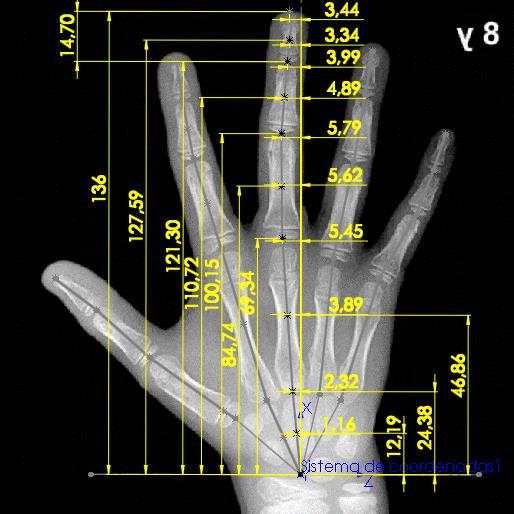

Dado que el proyecto se encuentra enfocado a modelar el comportamiento de una mano de un menor de 8 años, se hace necesario determinar las medidas estándar de la mano, para ello, se emplea un carpograma de un niño de 8 años Esta imagen médica permite realizar la evaluación del crecimiento del paciente basado en las longitudes, espesores y separaciones entre los huesos de la mano. Por ello, se desarrollan atlas que indican los procedimientos de análisis de las dimensiones de la mano y exponen imágenes de referencia para determinadas edades. De “Hand Bone Age A Digital Atlas of Skeletal Maturity” se extrae el carpograma de un menor masculino de 8 años el cual puede observarse en la Figura 11. (Gilsanz & Ratib, 2005)

Figura 11. Carpograma de referencia de paciente masculino de 8 años de edad

Fuente: (Gilsanz & Ratib, 2005)

Teniéndose el carpograma de referencia, se importa dicha imagen a SolidWorks, con el fin de realizar el análisis de dimensiones correspondiente. Primero se determinan los puntos de análisis para cada hueso de la mano, acorde a las recomendaciones dadas en “Hand Bone Age A Digital Atlas of Skeletal Maturity”, obteniéndose una imagen con puntos de referencia (Figura 12).

Los resultados de las mediciones realizadas sobre el carpograma de referencia se presentan en las Tablas 3, 4 y 5. Se emplea para esto la nomenclatura citada en la Tabla 2.

Tabla 3. Medidas de magnitud realizadas sobre el carpograma de referencia.

Pulgar [mm] Indice [mm] Medio [mm] Anular [mm] Meñique [mm]

Lt,D 15,19 Li,D 11,33 Lm,D 12,65 La,D 13,03 Le,D 10,96 Lt,P 20,93 Li,Mi 17,67 Lm,Mi 21,22 La,Mi 19,83 Le,Mi 13,84 Lt,M 30,74 Li,P 27,51 Lm,P 30,81 La,P 28,99 Le,P 21,58 Li,Me 46,53 Lm,Me 45,06 La,Me 40,21 Le,Me 37,66

De igual manera se mide la orientación de cada cadena cinemática respecto al eje X.

Tabla 4. Orientación de cada cadena cinemática sobre el carpograma de referencia

Ángulo [rad]

Pulgar -0,95

Indice -0,29

Medio -0,07

Anular 0,1 Meñique 0,31

Adicional a esto, se realiza la medición de las coordenadas (x,y,z) de cada uno de los vectores de orientación (u), que modelan la zona de los huesos carpos y que son el punto de partida para cada cadena cinemática (t, i, m, a, e), según la nomenclatura usada en la representación esquemática de la Figura 10.

Tabla 5. Coordenadas de los vectores de orientación.

utx 16,34 uix 21,91 umx 24,38 uax 23,55 uex 21,91 uty 0 uiy 0 umy 0 uay 0 uey 0 utz -19,14 uiz -9,9 umz -2,32 uaz 5,45 uez 11,69

Tomadas estas medidas se tiene completamente caracterizada la representación esquemática planteada con base en el carpograma de referencia de un niño de 8 años de edad, permitiéndose así la determinación de un modelo cinemático.